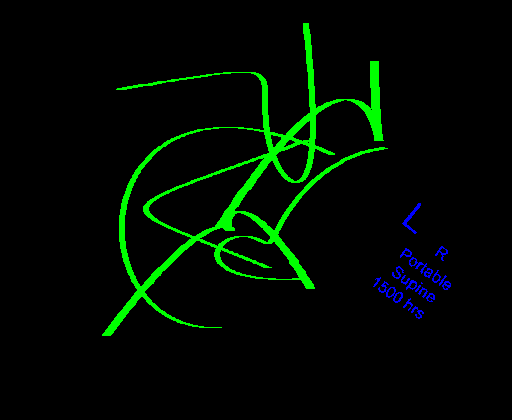

Automated catheter detection is a challenging task. Although most catheters have a radiopaque strip to facilitate detection, the strip may become less apparent depending on the projection angle. Catheters maybe confused by other similar linear structures like ECG leads and anatomy including ribs. Additionally, portions of catheters can be occluded by anatomical structures given that radiographs are a 2D projection of a 3D structure. For example, when a NGT is placed within the oesophagus, the catheter itself becomes less apparent due to the high density of the adjacent vertebrae. Finally, the number and type of catheters that could possibly appear in pediatric X-rays are unknown a priori. The catheters may be intertwined with each other thus making simple line tracing methods fail. Figure 1 gives three sample pediatric X-ray images with some common catheters highlighted in different colors.

To alleviate this annotation problem in catheter detection, we proposed to use X-ray images with simulated catheters by exploiting the fact that catheters are essentially tubular objects with various cross sectional profiles. To be more specific, a synthetic 2D projection of a catheter is generated by first simulating a horizontal catheter profile and then using it as a brush tip to draw along a B-spline path. This generated catheter is then composited with an X-ray image serving as the training data. Another contribution of this work is a segmentation network that can inherently take into account multi-scale information. This network adopts a UNet-style form and contains a recurrent module that can process inputs with increasing scales111Our code is available at https://github.com/xinario/catheter_detection.git.. We have empirically shown that by iterating through the scale space of the input image, higher recall is achieved as compared to using a single scale. Details about the methods are discussed in Section 3. Three sample detection results are shown in Figure 1.

The test dataset is collected locally and only contains frontal chest-abdominal X-rays from patients < 4 weeks old. This is the most common radiograph obtained to confirm placement of catheters such as UACs and UVCs in neonates. Currently, the test set has 35 fully labeled images with different catheter types with sample images previously shown in Figure 1. All the annotated catheters (lines excluding ECG leads) are treated as the same class in the detection.

Qualitative visual examples of the raw catheter likelihood maps obtained directly from the network without any postprocessing are shown in Figure 5. It can be seen that the proposed network at the highest scale (scale 3) achieves the best visual appearance as compared to the other methods. The maps from the proposed network at scale 2 and scale 3 look much cleaner than w/oR and fcn8s. We would attribute this to the iterative refinement of the detection results by using the recurrent module. When comparing results from the proposed network at different scales, we can see that the likelihood map from the smallest scale contains almost all line-like structures, including not only catheters but also ribs and ECG leads. This is because catheters, ribs, ECG leads look similar at a smaller scale. These irrelevant line-like structures are gradually filtered out in higher scales because catheters, especially UVCs and UACs, begin to appear as two parallel edges whereas ribs and ECG leads continue to appear as a single solid line.

There are certain situations where our proposed method would fail. Figure 7 (a) and (b) show a partially detected NGT. This mostly likely resulted from the decreased visibility of the radiopaque strip. Figure 7 (a) also shows another failure situation where the inferior portion of the UVC is occluded by the abdomen. (c) shows the case of a falsely detected unidentified line and (d) shows part of the lateral aspect of the rib cage falsely identified as a catheter.